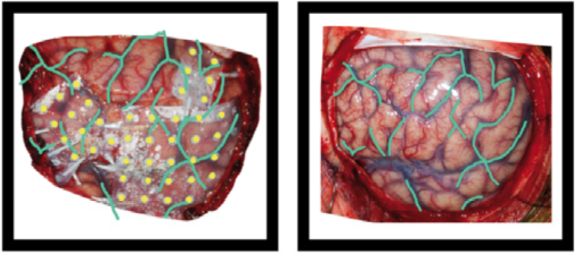

These can include photos of the electrodes on the brain surface, photos of anatomical features or landmarks (such as sulcal structure), and fiducials. Photos can also include an X-ray picture, a flatbed scan of a schematic drawing made during surgery, or screenshots of a brain rendering with electrode positions. The photos may need to be cropped and/or blurred to conceal identifying features or entirely omitted prior to sharing, depending on obtained consent.

Example of the operative photo of ECoG electrodes (here is an annotated example in which electrodes and vasculature are marked, taken from Hermes et al., JNeuroMeth 2010).

Below is an example of a volume rendering of the cortical surface with a superimposed subdural electrode implantation. This map is often provided by the

EEG technician and provided to the epileptologists (for example, see Burneo JG et al. 2014. doi:10.1016/j.clineuro.2014.03.020).